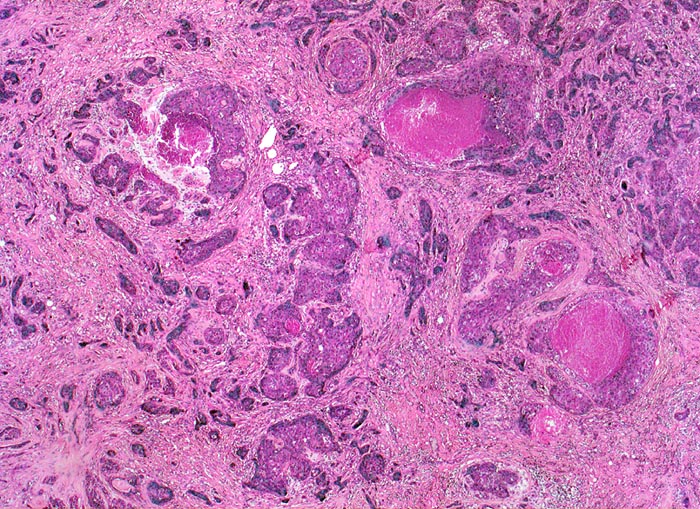

•  Invasives duktales Karzinom mit desmoplastischem Stroma rechts unten im Präparat.

•  Die Karzinominfiltrate bestehen aus schmalen soliden Zellsträngen, die keine Drüsenlumina ausbilden. Eine Myoepithelschicht fehlt. Kein assoziierter Mikrokalk.

• Mässig zahlreiche Mitosefiguren und Apoptosen.

• Die Karzinomzellen sind deutlich grösser als die normalen sekretorischen Zellen der nicht neoplastischen Drüsenazini. Die vesikulären Zellkerne sind vergrössert, pleomorph und hyperchromatisch. Die Kernmembran ist teils irregulär. Die Tumorzellkerne enthalten prominente eosinophile Nukleolen.

• Das Zytoplasma einiger Tumorzellen enthält runde bis ovale hyaline Globuli, teils umgeben von einem Halo (unspezifischer Befund).

• Das Karzinom ist gering differenziert: B.R.E. Grad 3; Score 8: 3, 3, 2. Keine Drüsenbildung: Score 3 Starke Zellatypien: Score 3 <10 Mitosen/10 HPF: Score 2

• In den bindegewebigen Ausläufern dilatierte Gangstrukturen mit peritumoralem duktalem Carcinoma in situ mit hohem Kernmalignitätsgrad (Grad 3, kribriformer und solider Typ mit Komedonekrosen, kein assoziierter Mikrokalk). Erhaltene Myoepithelschicht im Bereich des in situ Karzinoms.

• Läppchenkanzerisierung (Ausbreitung des Karzinoms in den Azini der Drüsenläppchen).

• Peritumorale Arterie mit assoziiertem dilatiertem Lymphgefäss mit intraluminalem Tumor (Lymphangiosis carcinomatosa).